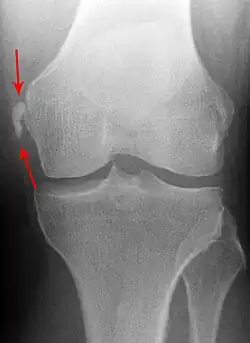

Pellegrini-Stieda Syndrome, shown as marked on the imaging.

Diagnosis is typically made on radiographs demonstrating the Pellegrini-Stieda syndrome sign accompanied by pain or restriction of range-of-motion of the knee joint.[2] Pellegrini-Stieda syndrome sign is typically described by a longitudinally linear opacity, which is a process that is describes characteristic of calcification in the soft tissue located medial to the medial femoral condyle.[2] This calcification seen on imaging represents the ossification of the medial collateral ligament, which typically does not develop until approximately three weeks after the initial injury.[2]It is important to note to distinguish this radiographic finding from that of a medial femoral condyle avulsion fracture, which is an injury in which a pulling force of a tendon or ligament fractures away a piece of the bone from its attachment site.[2]